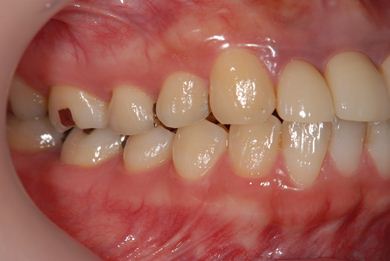

治療前

• 治療前